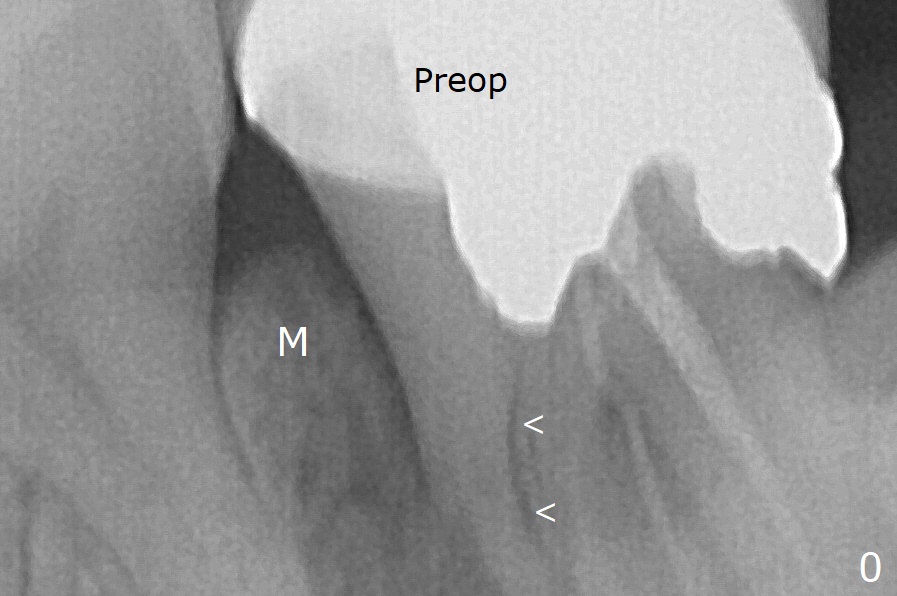

In fact the mesial crest is resorbed 3.5 months postop (Fig.9 M, as compared to that of preop and immediate postop in Fig.0,1). Continuous resorption may be associated with food impaction when a permanent crown is delivered. The preventive remedy would be socket shield, mesial and distal (Fig.0' M, D).